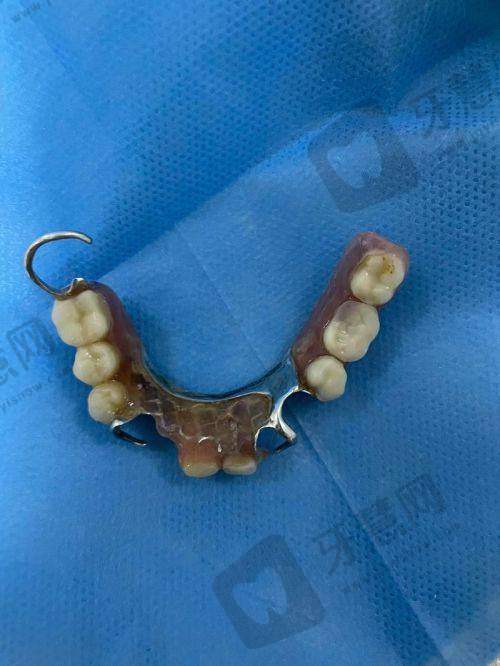

特色项目众多。北京欢乐英辰口腔门诊部拥有多个特色项目。在牙齿正畸项目方面,采用精良的隐形正畸技术,这种技术使用的隐形牙套几乎完全隐形,不影响患者的美观和社交,而且牙套可以自行摘戴,方便患者清洁口腔,减少了牙齿脱矿、龋坏等问题的发生。同时,医生会根据患者的牙齿移动情况,精细调整牙套的力度和方向,确保正畸成效更加理想。种植牙项目,门诊部引进了国内外精良的种植系统,种植过程中,医生凭借不错的技术,能够精细植入种植体,缩短手术时间,减少患者的痛苦。种植体与牙槽骨的结合紧密,稳定性高,使用寿命长,能够为患者修复良好的咀嚼功能。牙齿美白项目,采用安心有效的美白技术,美白剂对牙齿的刺激性小,能够在短时间内让牙齿变得洁白亮丽,而且美白成效持久,让患者拥有自信的笑容。